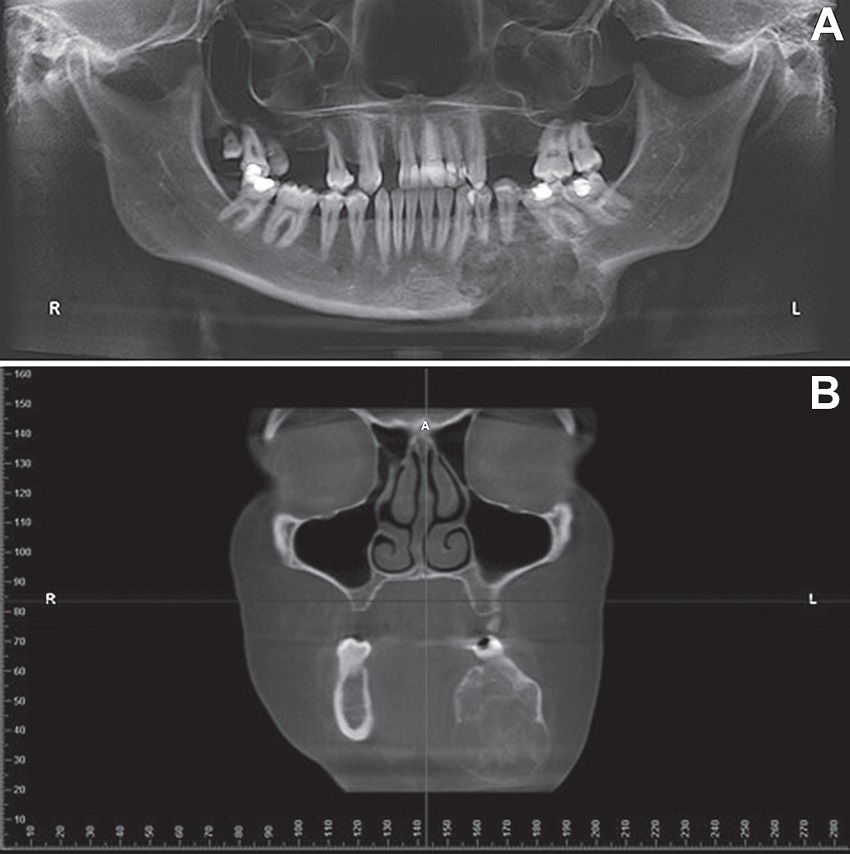

A) panoramic radiograph showing a multilocular radiolucent image in the left mandibular body region, involving teeth 34, 35 and 36 with discrete root resorption; B) CT, coronal section, showing hypodense lesion expanding the cortical bone.

CT: computed tomography.